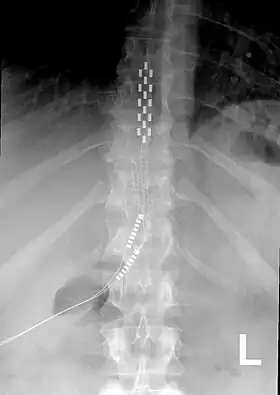

![]() Anterior view X-ray of a spinal cord stimulator (SCS) implanted in the thoracic spine |